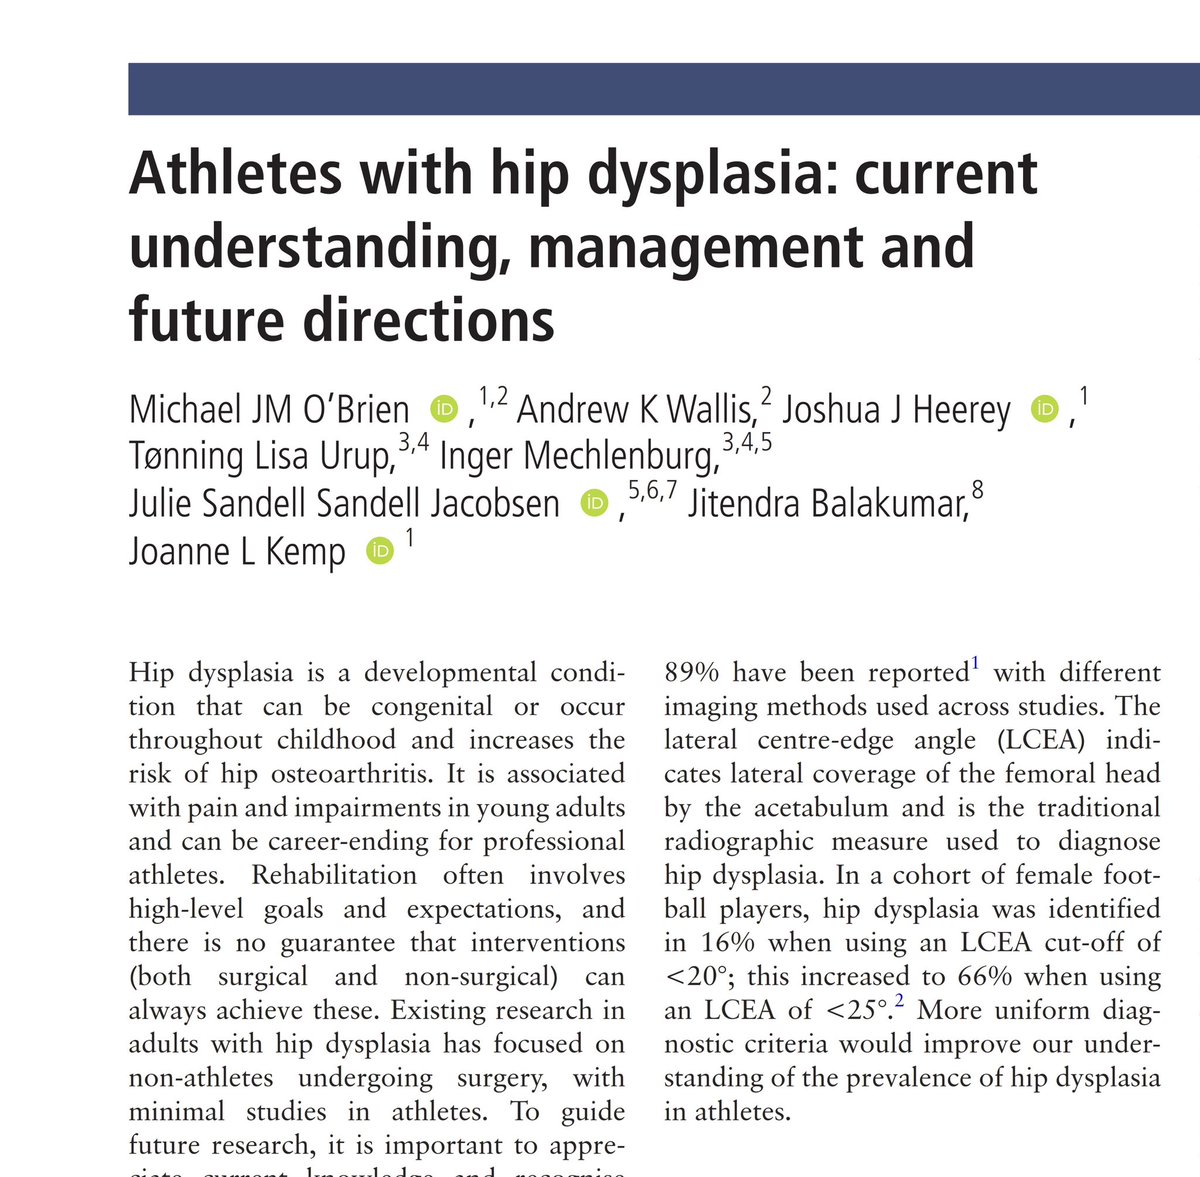

Athletes with Hip Dysplasia: current understanding, management and future directions 🏃🏽♂️🤸♀️ New Editorial in British Journal of Sports Medicine (BJSM) bjsm.bmj.com/content/early/… Huge thanks to my co-authors: Andrew Wallis Dr Joshua Heerey Julie S Jacobsen Jit Balakumar Dr Joanne Kemp Lisa Tønning & Inger Mechlenburg